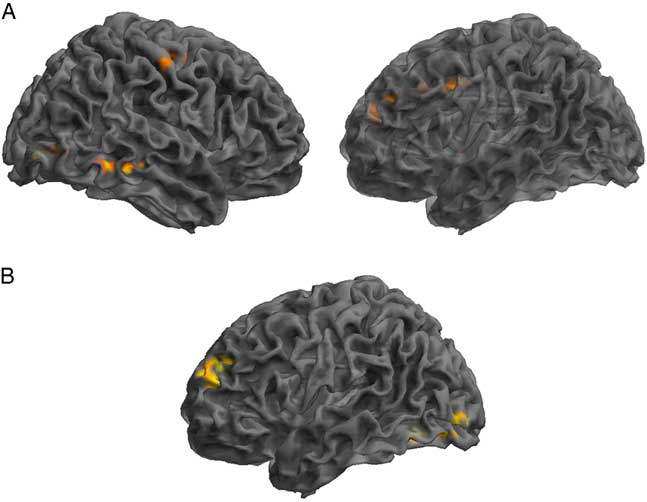

GICA Results: SRC Group Post-concussion Over Time

Assessment of the SRC group at time 1 (acute phase of SRC) compared to time 2 (when SRC symptoms should be resolved), revealed greater functional connectivity in the DMN components at time 1 compared to time 2 within the right IFG, MTG, precentral gyrus, and angular gyrus (AG), and left lingual gyrus, MFG, and middle cingulate gyrus (MCG). Decreased connectivity at time 1 compared to time 2 was found within the left anterior prefrontal cortex and MOG (Table 3; Figure 2).

Fig. 2 Significant changes in functional connectivity from time 1 to time 2 in the SRC group. (A) Greater connectivity and (B) reduced connectivity in the SRC group from time 1 to time 2. (A) Shown: right MTG, right precentral, left lingual gyrus, left MFG, left middle cingulate; Not shown: right angular gyrus. (B) Shown: left anterior PFC and MOG.

Table 3 Changes across time within the DMN component derived using GICA, assessing SRC group at time 1 compared to time 2

Time 1>Time 2 indicating brain regions with greater functional connectivity at time 1 compared to time 2 and Time 1<Time 2 indicating reduced functional connectivity at time 1 compared to time 2.

L=left hemisphere; R=right hemisphere; BA=Brodmann area; MOG=middle occipital gyrus; IFG=inferior frontal gyrus; MFG=middle frontal gyrus; MTG=middle temporal gyrus; PFC=prefrontal cortex.